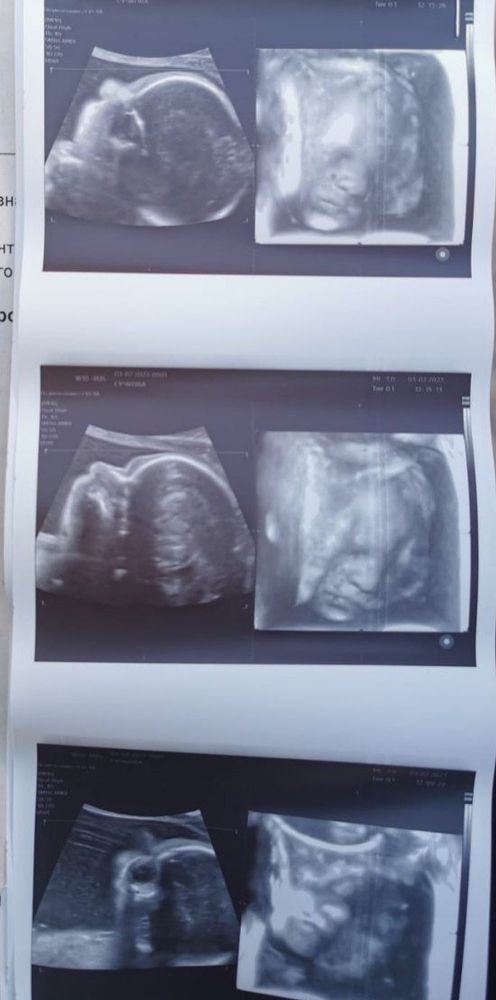

4D узи (оставлю на память)

Не могу налюбоваться нашей прелестью, смотрю и мне не верится, что во мне почти целый килограмм счастья, которое мы ждали целых 7 лет (если быть точнее, намеряли по узи 971грамм)

Долго пришлось уговаривать Вероничку открыть личико, постоянно отворачивалась от датчика, лупила по нему со всей мощи либо же старалась прижать личико к дну матки так, чтобы снять чёткую картинку не удалось. 😄 Малышка по всем параметрам обгоняет ровно на неделю. По месячным срок 25+2,по узи 26+2. На узи ходили всей семьёй, муж, сын и я. Сын остался под большим впечатлением,был очень рад увидеть сестрёнку ❤️

Следующее узи будет плановым в 30 недель, ДМЖП 3мм пока так и оставили, надеюсь закроется к 30 неделькам🤞🙏

Думаю, если бы я ещё недели 2 потерпела, ей бы уже места совсем не осталось, и не удалось бы её заснять хотя бы так, меня 40 минут крутили-вертели, чтобы хоть как-то её поворочать. Она постоянно голову к стенке прижимала и не получалось заснять.